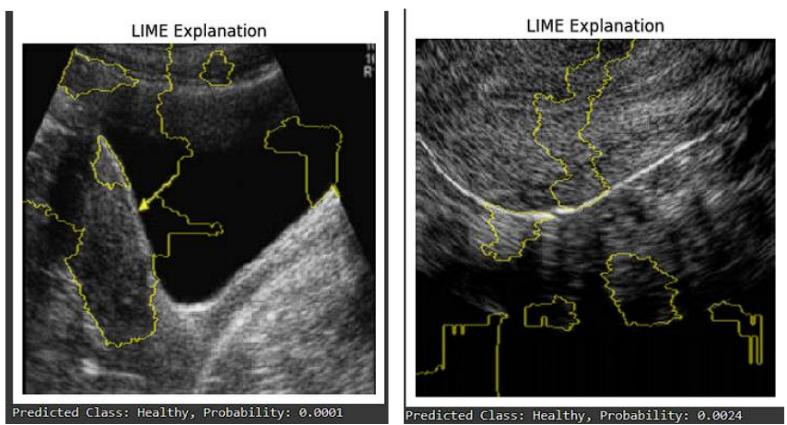

Sample predictions from the validation and test dataset are shown below along with their LIME explanations:

Figure 4: Comparison of LIME explanations for a correctly classified validation image (left) and test image (right). In both instances, the model accurately predicted Healthy, with LIME highlighting key regions which model focus on.

This approach provides valuable insights into how the model arrives at its predictions, enhancing interpretability and trust in its decisions. By visualizing the contributions of different parts of the image, healthcare professionals can better understand the rationale behind the model’s classifications. This transparency is particularly important in medical applications, where understanding the basis for a diagnosis can guide further clinical decision-making.

The use of LIME helps to demystify the model’s behavior, allowing users to see which features were pivotal in determining whether an ultrasound image was classified as healthy or unhealthy. This not only aids in validating the model’s performance but also fosters confidence among practitioners who may rely on automated systems for diagnostic support. Overall, integrating LIME explanations into the prediction process enhances the interpretability of deep learning models in medical imaging contexts, ensuring that they are not only accurate but also comprehensible to end-users.

The inclusion of LIME explanations (Figures 4 and 5) provides crucial insights into the model’s decision-making process. By visualizing the image regions that most strongly influenced the predictions, we gain a level of transparency that is essential in medical applications. This interpretability allows clinicians to understand *why* the model made a particular prediction, fostering trust and facilitating integration into clinical workflows. While we have provided examples, a more comprehensive analysis of LIME explanations across a larger and more diverse test set would further strengthen the understanding of the model’s behavior.